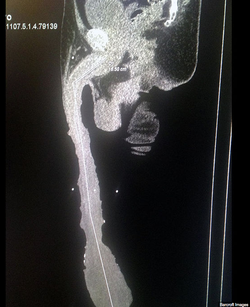

One doctor, who examined him to verify the size of his genitals, Dr Gonzalez said: “He began with this enlargement since he was a teenager, wrapping some bands around his penis with some weights and trying to stretch it.”